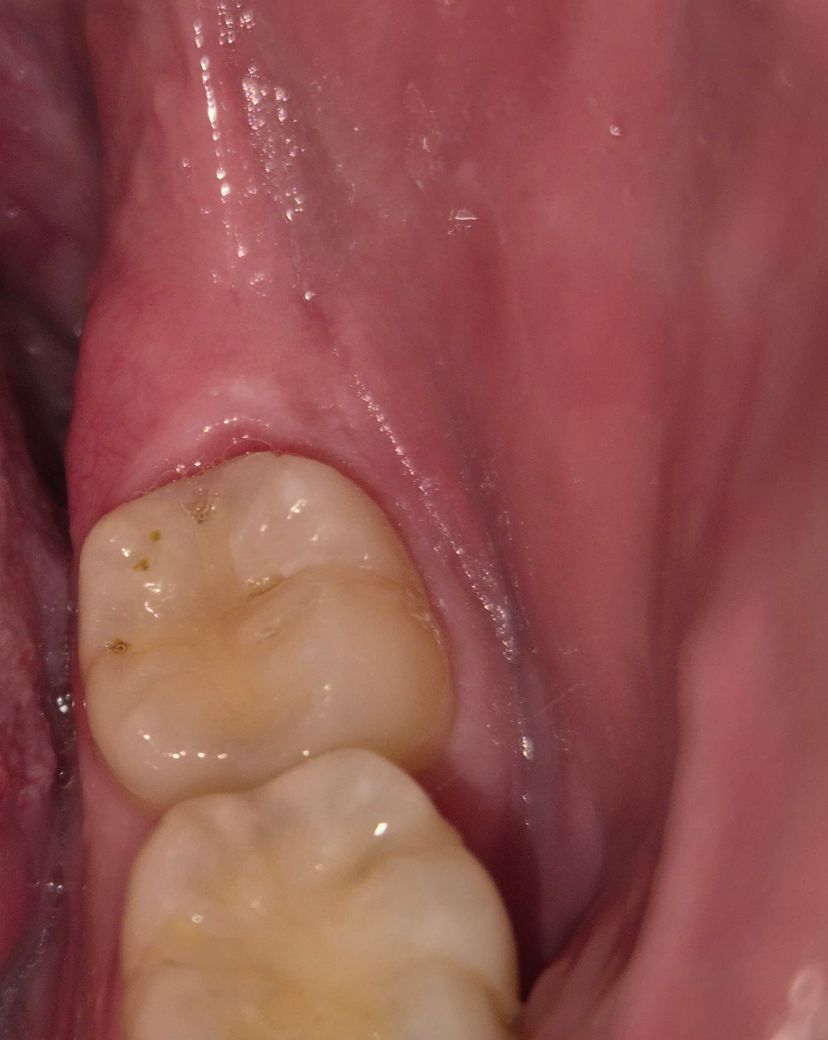

치아에 작은 구멍이 나있습니다 ㅠㅠ 이정도면 어느정도까지 치료할까요?

사진에 보이는것처럼 작은 구멍들이 어금니에 생겨 있습니다. 통증은 크게 없습니다.

병원가보려는데 신경치료까지 해야할까요?

• 1번 째 사진